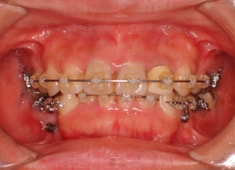

治療後(3年2ヶ月後)